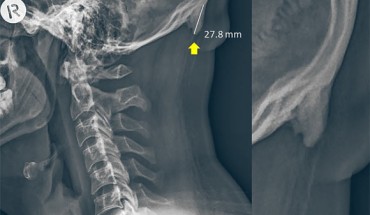

Aberrant postures have led to an increase in young adults developing a bone growth at the back of the skull, according to a study by University of the Sunshine Coast scientists. A radiograph of a 28-year-old male participant. Image credit: Shahar & Sayers, doi: 10.1038/s41598-018-21625-1. In 2016, University of the Sunshine Coast researchers David Shahar and Mark Sayers analyzed X-rays of 218 young Australians (18-30-year-old) and found that 41%...